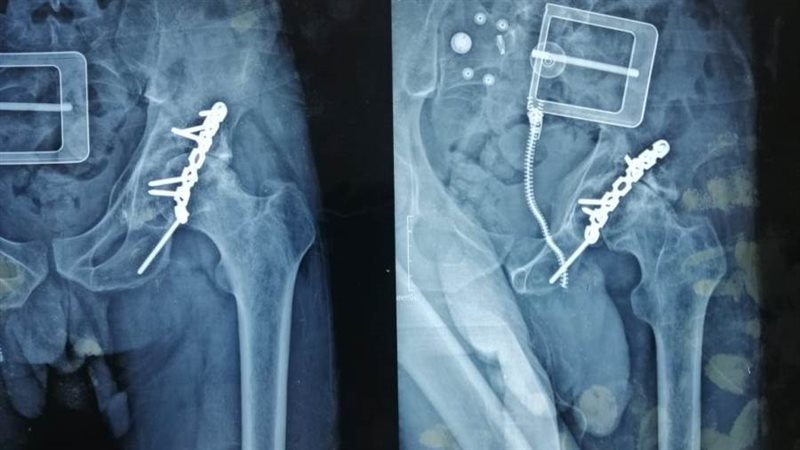

وكان المستشفى استقبل مريض يبلغ من العمر 30 عاما، ويعاني من كسر قديم في حق مفصل الحوض مثبت سابقا بشريحة ومسامير، مع وجود إصابة جزئية في العصب الوركي منذ أكثر من خمس أعوام أدت إلى خشونة حادة و تآكل في مفصل الفخذ، مع وجود عرج واضح بالمشي.

وتم وضع المريض ضمن الحالات الحرجة لقوائم الانتظار، حيث تمكن الفريق الطبي من إجراء استبدال مفصل فخذ صناعي كامل، واستغرقت العملية حوالي ثلاث ساعات، وتعد من الجراحات المتقدمة ذات المهارة الخاصة.